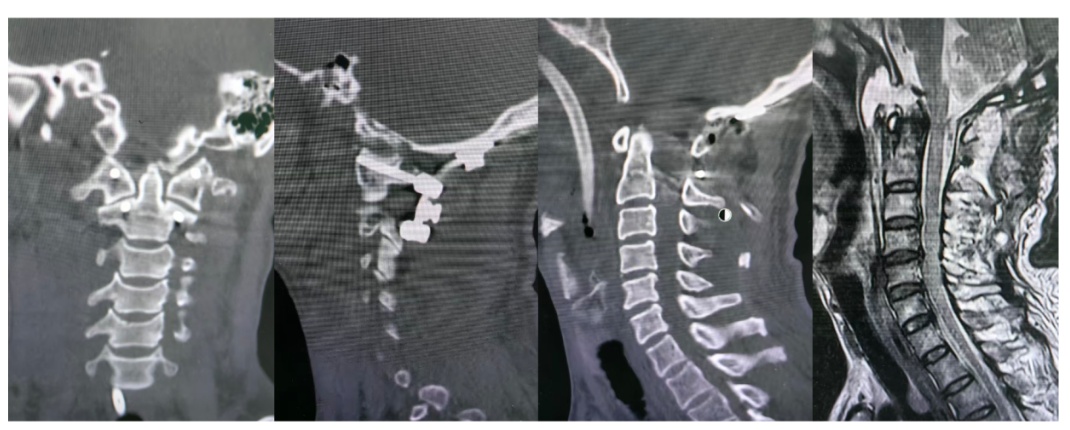

▲术后病情稳定后的即刻复查:寰枕关节已复位,延髓及上颈髓无压迫

在神经外科、ICU等多学科努力下

黄伯生命趋向稳定

迎来手术时机

江晓兵带领广医二院颈椎医疗组

在麻醉科和手术室精密配合下

为患者进行了寰枕关节复位固定手术

术中

医生在透视的精确引导下

将完全脱位的关节精准复位

为被压迫的延髓和脊髓“松绑”

随后用钉棒内固定系统

在寰椎与枕骨间构建起坚固“桥梁”

永久性地重建了头颅与脊柱的稳定性

杜绝了再次脱位的风险